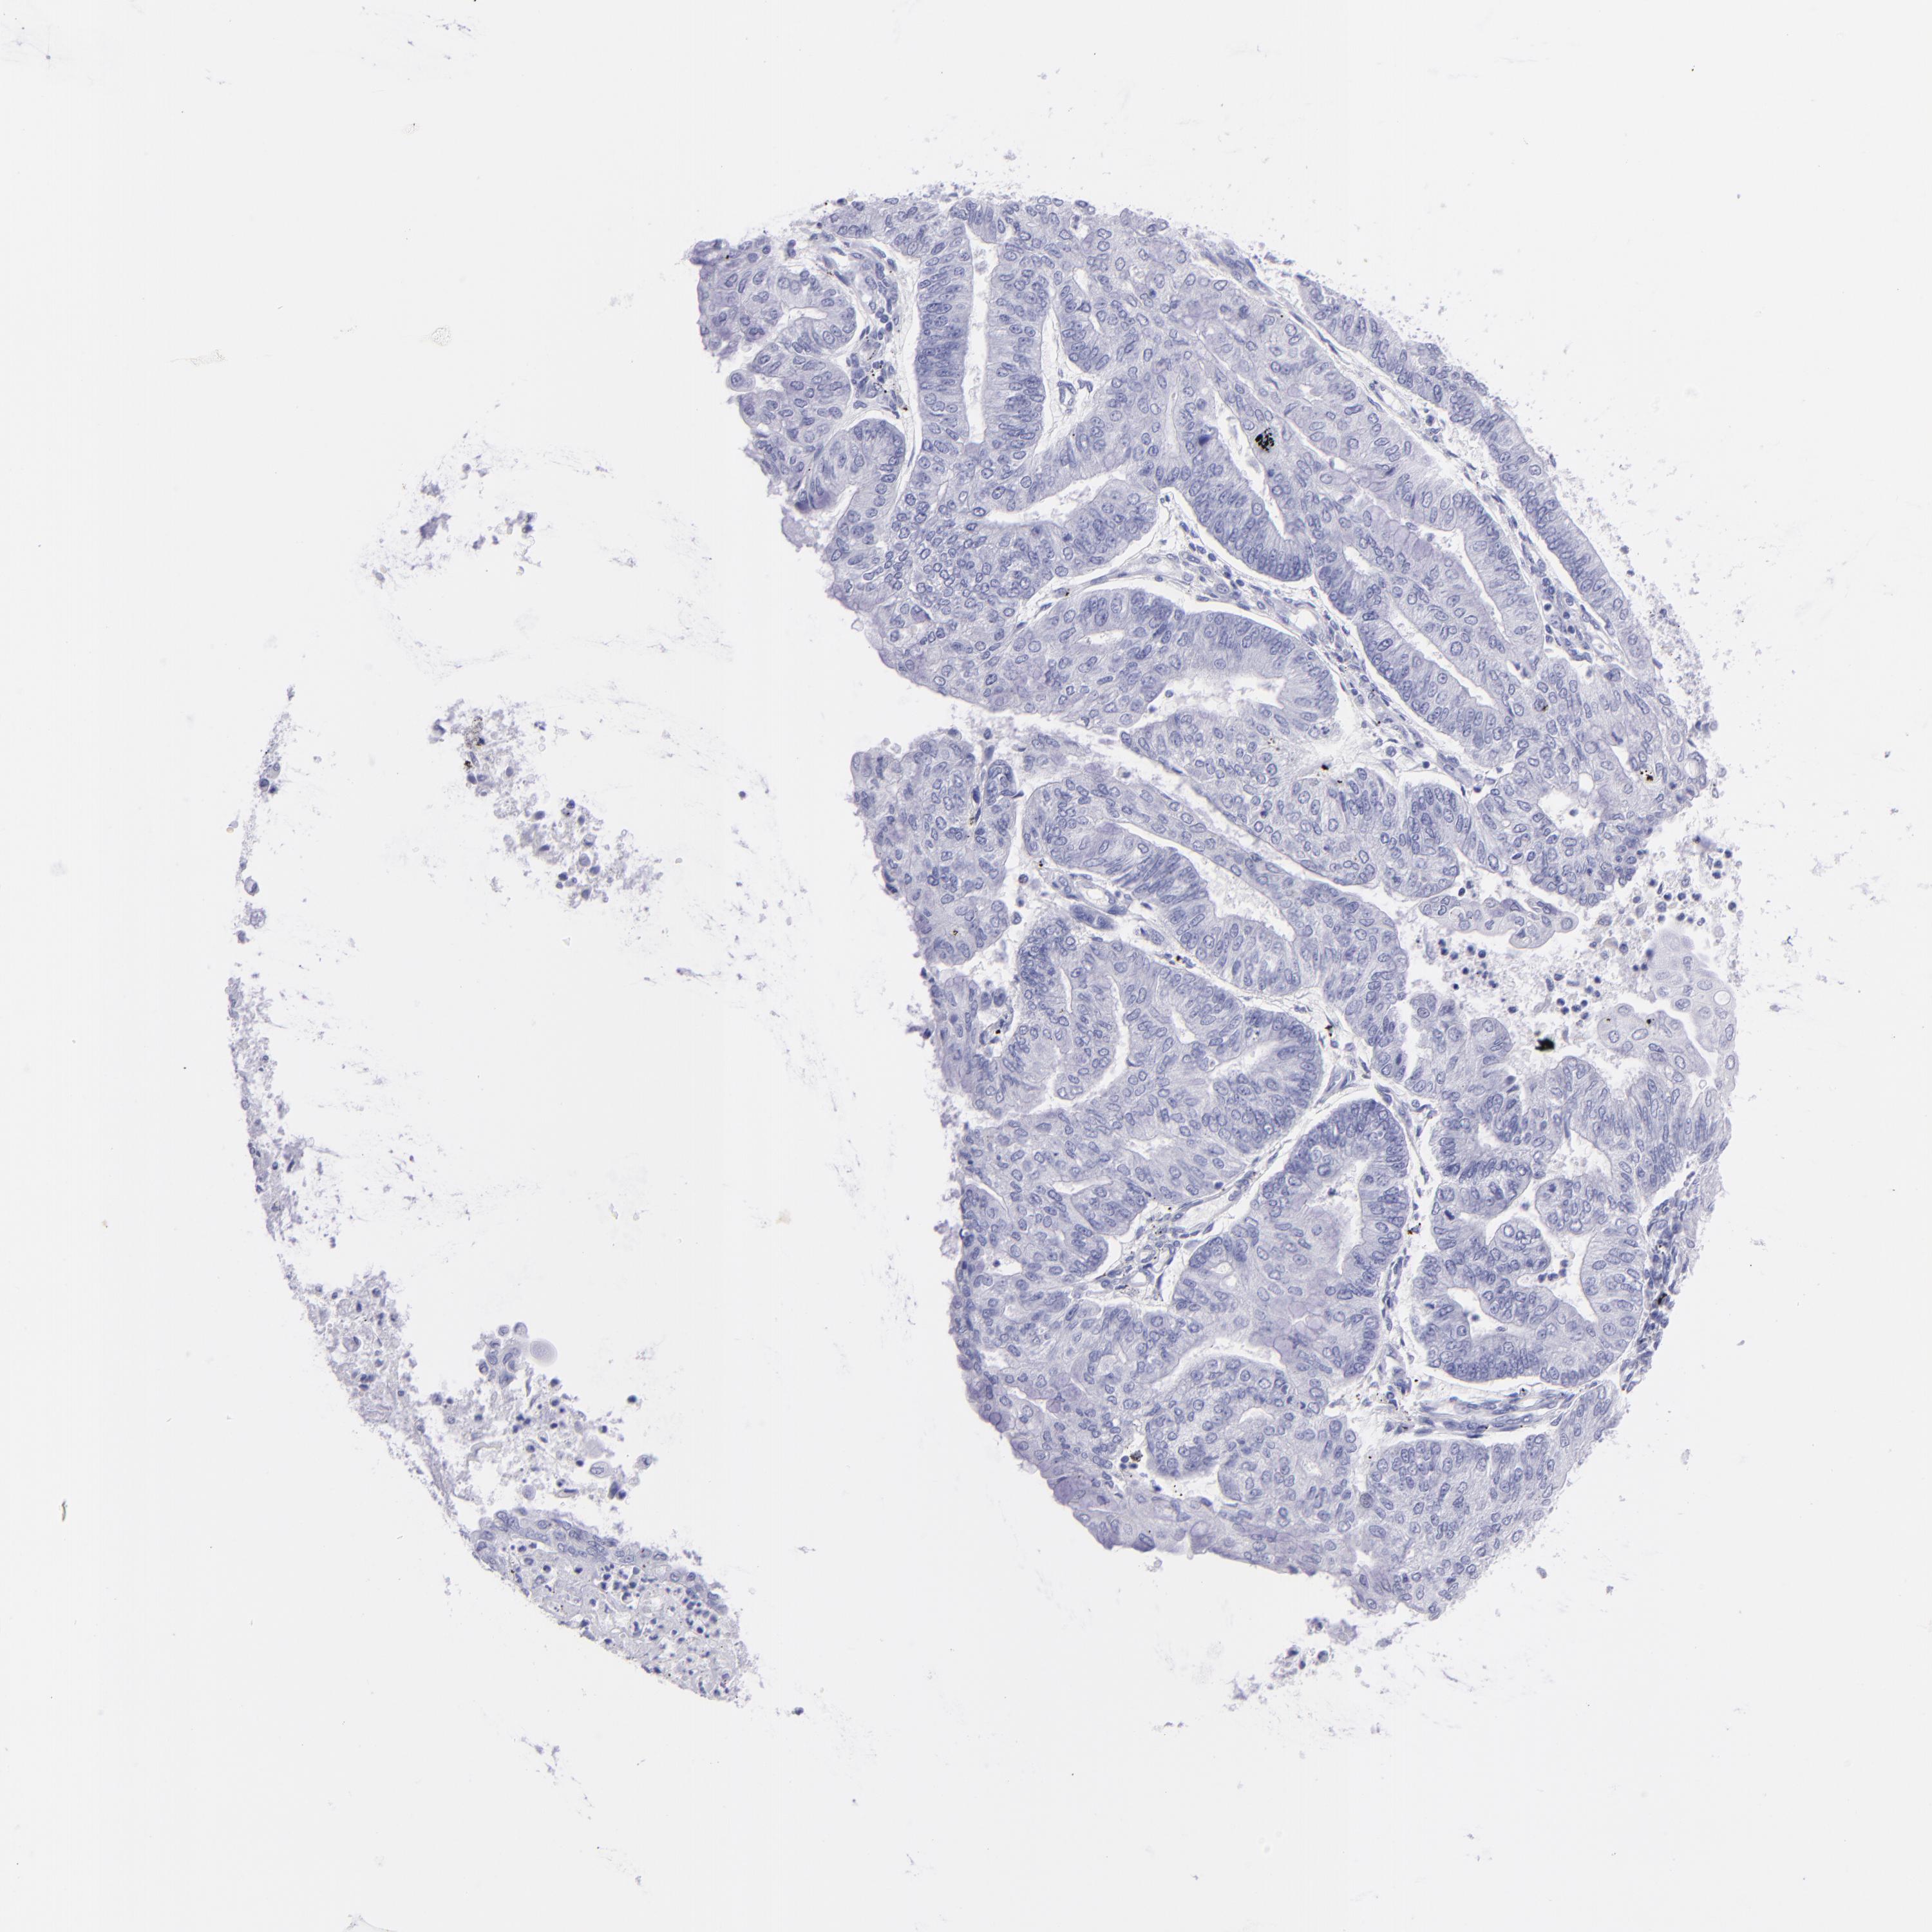

ENDOMETRIAL CANCER - Protein expressioni

A mouse-over function shows sample information and annotation data. Click on an image to view it in a full screen mode. Samples can be filtered based on level of antibody staining by selecting one or several of the following categories: high, medium, low and not detected. The assay and annotation is described here.

Note that samples used for immunohistochemistry by the Human Protein Atlas do not correspond to samples in the TCGA dataset.

Antibody stainingi

Antibody staining in the annotated cell types in the current human tissue is reported as not detected, low, medium, or high, based on conventional immunohistochemistry profiling in selected tissues. This score is based on the combination of the staining intensity and fraction of stained cells.

Each image is clickable and will lead to virtual microscopy that enables deeper exploration of all samples and also displays staining intensity scores, fraction scores and subcellular localization as well as patient and tissue information for each sample.

Adenocarcinoma, NOS

Adenoma, NOS

Adenocarcinoma, metastatic, NOS

Neoplasm, malignant, NOS